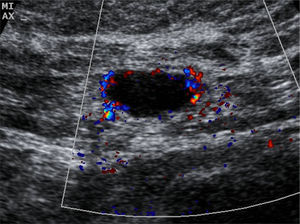

The US parameters evaluated were: cortical thickness, morphological changes in the hilar fat and characteristics of the cortical vascular flow. The following were considered findings suspicious for metastasis: local or diffuse cortical thickness ≥3mm (Fig. 1), absence, obliteration or eccentric location of the hilar fat (Fig. 2), and/or non-hilar cortical vascular flow (NHCVF) (Fig. 3) on color Doppler-duplex US with parameters set for low velocity flow detection (pulse-repetition frequency at 488, velocity scale at 3cm/s), and individualized setting for the rest of parameters. CNB was performed in those lymph nodes showing one or more of these parameters. When several lymph nodes showed US abnormalities, the most suspicious node was sampled, considered as the one with the largest number of parameters indicative of metastasis. At an equal number of parameters, the absence of hilar fat was the prevailing criterion in the selection of the lymph node, since this is the parameter with the highest positive predictive value (PPV) described in the literature.12,21,22 None of the patients in our series had several suspicious lymph nodes with one single US finding different in each lymph node. Access to the lesions was not a limitation for CNB in any of the patients.

Cortical thickness >3mm was found in 21 (78%) of the 27 patients with negative CNB; morphological changes in the hilar fat were found in 2 patients (7%), and NHCVF in 8 patients (30%), with 2 or more US criteria of metastasis found in several lymph nodes. Of the 50 patients with positive lymph nodes (positive CNB or negative CNB with positive sentinel node), cortical thickness was found in 44/50 patients (88%), changes in the hilar fat in 20/50 patients (40%) and NHCVF in 29/50 patients (58%). Considered individually, the absence or obliteration of the hilar fat was the US parameter with the highest PPV (90%) against NHCVF (78%) and cortical thickening (68%). The combination “cortical thickening and NHCVF” was positive in all cases detected in our series (100% PPV) (Table 1).

Abe et al.12 have reported that the presence of NHCVF may be a good indicator of nodal metastasis, with a high PPV (78%) when is detected in patients with ipsilateral breast cancer. We obtained the same value in our series. This increased NHCVF is probably due to increased peripheral vascularity relative to decreased hilar blood supply that results from infiltration by metastatic disease.26

In the study by Abe et al., the absence of hilar fat was the US finding with the highest predictive value followed by “cortical thickening combined with NHCVF”, with a PPV of 81%. In our series, all the lymph nodes with “increased cortical thickness and NHCVF” were metastatic, indicating a high PPV (100%). This difference may be due to the smaller sample size and to the minimal dependency on the operator of the US study and of axillary lymph node biopsy in our series. Abe et al. included patients from several medical institutions in their study.